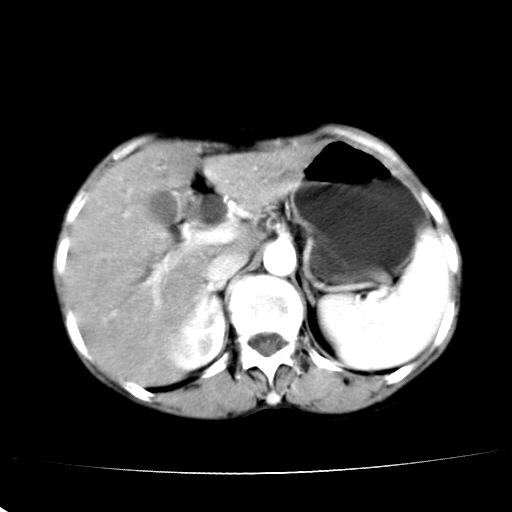

以下是引用jiangjing在2008-6-3 13:36:00的发言:[br]支持 胰头癌------肝内外胆管扩张,胰管扩张,胰头增大,增强见结节状轻度强化影,双管征明显

以下是引用卜一在2008-6-3 14:40:00的发言:[br]支持:胰头癌!(肝内外胆管扩张,胆囊高度扩张,胰管扩张,胰头增大,增强见结节状强化,明显低于胰腺强化密度,并明显见双管征)

以下是引用dyqct在2008-6-3 14:54:00的发言:[br]支持 胰头癌伴肝内外胆管扩张,胰管扩张,胰头增大,增强见结节状轻度强化影,双管征明显。肠系膜上静脉已受侵(已不能手术),建议离子植入治疗吧。